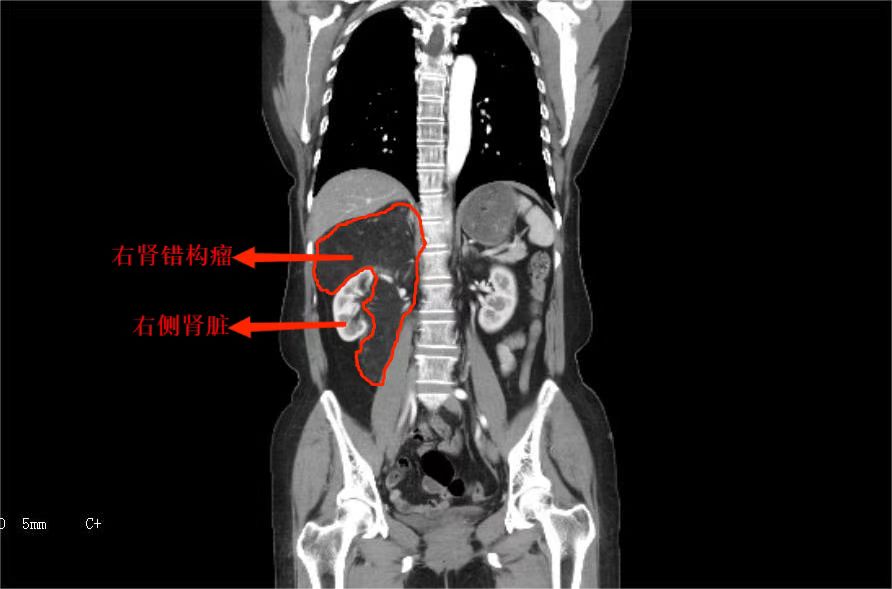

入院后,杨科主任团队为刘女士仔细检查,发现其右肾被“7”字型肿瘤包裹压迫,已经明显移位。这给手术带来挑战,肾脏是血管非常丰富的器官,肾脏血流占心脏排出血量的1/4,如果切除肿瘤同时保留肾脏,手术难度非常大、操作复杂、出血风险高,很有可能出现失血性休克,甚至死亡。经过完善的术前准备,刘女士被送进手术室,术中可见肿瘤紧紧地包裹着肾脏,两者合为一体,周围滋养血管丰富,并且肿瘤深入肾蒂,肾蒂血管在肿瘤中穿行,大量分支为肿瘤供应血运。经过一番努力,手术成功切除肿瘤,并保住了右侧肾脏。

术后,刘女士恢复良好,今日康复出院。杨科主任介绍,刘女士的巨大肿瘤为右肾错构瘤,肾错构瘤又称为肾血管平滑肌脂肪瘤,是由异常增生的血管、平滑肌及脂肪组织按照不同比例构成的,主要发生于成年人,平均发病年龄为40岁左右,女性较为多见,可以引发腰腹部疼痛、血尿甚至休克等临床表现。